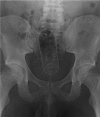

Management of rectal foreign bodies: description of a new technique and clinical practice guidelines

A number of techniques have been described to remove rectal foreign bodies. In this report, a novel endoscopic technique using a pneumatic dilatation balloon normally used in achalasia patients is presented. In addition, a systematic review of the literature was performed for non-operative methods to remove foreign bodies from the rectum. These results are summarised, presented as a practical at-a-glance overview and a flow chart is offered to guide the clinician in treatment decisions. The design of the flow chart was based on the aims to treat the patient preferably on an outpatient basis with minimally invasive techniques and if possible under conscious sedation rather than general anaesthesia.